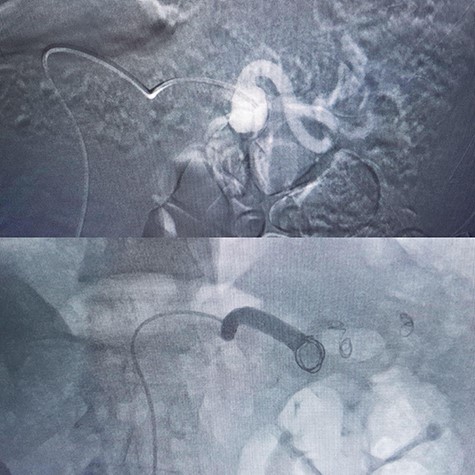

| 5 | Male | 52 | 6 cm | Hybrid surgery (proximal control by balloon + aneurysm resection (Fig. 4) | Proximal | Discharged |

In a 52-year-old man (third patient), 3-cm SAA was found incidentally in ultrasound and CTA. According to size of the aneurysm, he was candidate for endovascular treatment. Angiography and positioning of the coils on either side of the aneurysm (‘sandwich technique’) was completed (Fig. 3). Post-embolization checks were performed with selective splenic, celiac and superior mesenteric artery angiograms to confirm occlusion of the main splenic artery and patency of the collateral arteries. All seven patients discharged with no procedure-related complications.